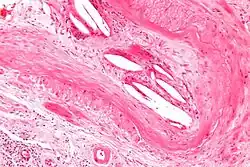

| Micrograph showing a cholesterol embolus in a medium sized artery of the kidney. Kidney biopsy. H&E stain. | |

The microscopic examination of tissue (histology) gives the definitive diagnosis. The diagnostic histopathologic finding is intravascular cholesterol crystals, which are seen as cholesterol clefts in routinely processed tissue (embedded in paraffin wax).[7] The cholesterol crystals may be associated with macrophages, including giant cells, and eosinophils.